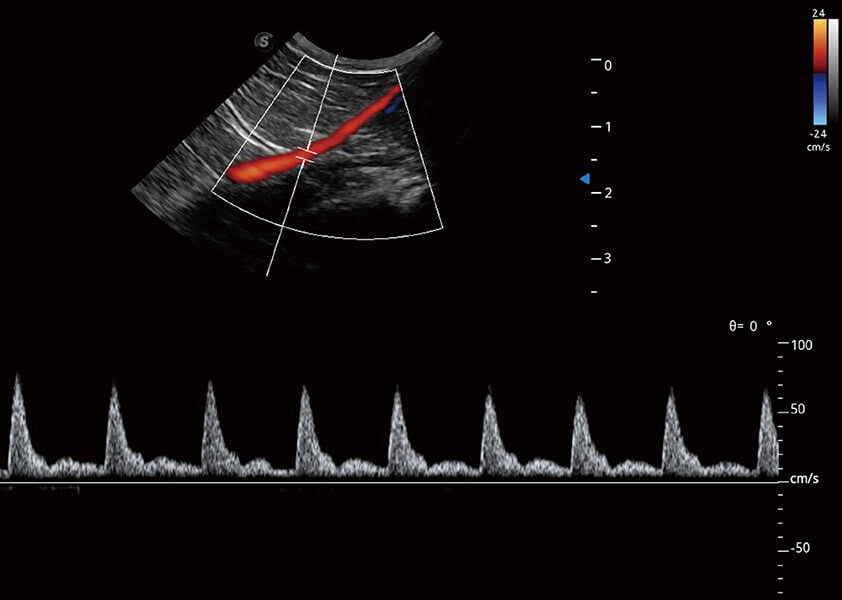

ProPet 60 作為一款高端臺式動物超聲設(shè)備,為動物醫(yī)生的日常診斷提供了一系列貼合動物臨床需求、解決臨床實(shí)際問題的高級成像功能。憑借全系列高清探頭,滿足醫(yī)生對腹部、心臟、生殖、淺表、肌骨等成像的所有需求,切實(shí)幫助您提升檢查效率,提高診斷信心。